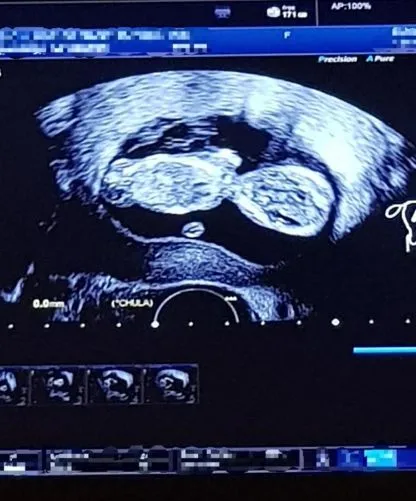

วันนี้จะพาทุกท่านไปชมภาพน่ารักของ แนนซี่ ที่ตอนนี้เธอแต่งงานมีครอบครัวที่อบอุ่นไปแล้วยังมีอีกหลายคนที่ทั้งรักและคิดถึงทั้งสองคนแฟนคลับยังคงจำได้ดีเลย วันนี้เธอกำลังเป็นคุณแม่แล้วแฟนคลับต่างเข้ามาแสดงความยินดีกับเธอเป็นจำนวนมากบอกเลยว่า เป็นเรื่องที่น่ายินดีเป็นอย่างมาก เอาเป็นว่าเราไปชมภาพน่ารักของแนนซี่กันเลยดีกว่าเป็นว่าที่คุณแม่ที่สวยมากจริงๆ